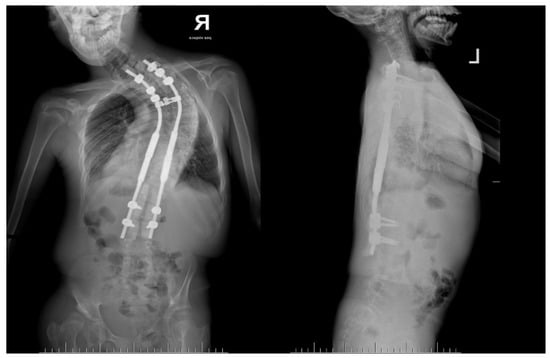

Figure 5.

Radiological standing X-rays AP and LAT of 14-year-old boy at 1 year of follow-up showed correction of main curve from 130 degrees to 80 degrees.

A 14-year-old boy was admitted to our clinic due to rapidly progressing scoliosis. He had previously been treated by other physicians and had an extensive history of conservative treatment of spinal deformities, including the use of a Cheneaux brace. Despite all the efforts made, the scoliosis continued to progress. During a visit to our clinic and examination, we revealed a spine curvature of 130 degrees (Figure 1 and Figure 2). The boy used a wheelchair due to severe walking problems. He was able to walk about 50–100 m on his own, but he developed pain in his spine and the left hip joint, which was dislocated. Although the boy was 14 years old, his mental development could be estimated at the age of a seven-year-old child. Additionally, we diagnosed that both of his feet were deformed, flat-valgus, making walking difficult, and had not been treated so far. Contractures were also revealed in all joints of the upper and lower limbs, slightly limiting mobility. However, the biggest functional problem was severe scoliosis, which was stiff and correctable only in about 30 percent. We recommended tests to prepare for and qualify for spine surgery. Spinal MRI diagnosed Chiari II syndrome and syrinx (Figure 3). This patient underwent foramen magnum decompression 3 months before planned surgical correction for severe scoliosis. Then, due to severe scoliosis of 130 degrees, bone immaturity and insufficient T1–T12 dimensions, the patient was qualified for surgical treatment using magnetically controlled growing rods (MCGR), due to surgical technique described in the literature [,,]. Other less invasive techniques for traction spinal deformities [,,,], such as halo gravity traction (HGT), could not be used due to the fact that HGT treatment is contraindicated in the presence of spinal pathologies such as syrinx, spinal tumors, increasing the risk of neurological complications during HGT course. Also, instability of the spine in the occipital–cervical and cervical region disqualifies the patient from such treatment. In our case, the patient underwent Chiari II syndrome decompression and had syrinx. For this reason, we considered MCGR treatment to be the least invasive [,]. We did not consider anterior release because it is a rather antiquated technique and the superiority of other methods of surgical treatment without disturbing the continuity of the chest has been proven [,,,,,]. This solution was very good for the patient because our surgical technique provided minimal surgical technique, implantation of screws and rods through two small incisions, and correction by distraction under the control of spinal cord neuromonitoring (Figure 4) []. In the period after MCGR implantation and subsequent spine surgery, pediatric orthopedists performed two foot deformation correction surgeries (Figure 5). After spine surgery using MCGR, we gradually performed MCGR distraction over the next 2 years, and after no further distractions were possible, we performed the final surgery, conversion to PSF with simultaneous multi-level Ponte osteotomy, which gave a very good and satisfactory surgical result []. In the perioperative period, two serious complications occurred: pneumothorax caused by central catheter, and gastrointestinal bleeding due to previously undiagnosed gastrointestinal varices. Pneumothorax was treated with pleural drainage (3 days), and bleeding from the gastrointestinal tract was treated gastroscopically. Finally, the patient was placed in an upright position on the 4th postoperative day and left the hospital on the 8th postoperative day, with full satisfaction with the treatment. The patient was monitored on an outpatient basis every 3 months. After the surgery, his body’s performance improved significantly and his spine pain decreased. T1–T12 height and T1–S1 improved from 156 mm and 268 mm preoperatively, respectively, to 194 mm and 332 mm after MCGR placement, respectively, and 215 mm and 368 mm after definitive surgery and posterior final fusion. He can walk about 2 km a day without any pain (Figure 6 and Figure 7).